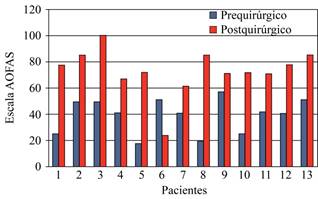

En la escala AOFAS el promedio prequirúrgico obtenido fue de 39.3 (± 13.1) en comparación con el postquirúrgico a seis meses de 73.4 (± 18) (Figura 5).

La inestabilidad constituye una incapacidad funcional en especial en personas con altos niveles de actividad que limita la vida diaria. Existe gran controversia acerca del tratamiento conservador contraquirúrgico. Se han establecido indicaciones precisas para la realización de éste. En un estudio de 39 voluntarios con diagnóstico de inestabilidad mecánica crónica, 20 de ellos se manejaron mediante reconstrucción ligamentaria con la técnica de Chrisman-Snook y los 19 restantes con ejercicios de rehabilitación. Se hizo una valoración a todos ellos, aplicando la escala AOFAS previo a su manejo y en un plazo entre seis a 18 meses. Se concluyó que la reparación quirúrgica ha resultado más efectiva que el manejo conservador basado en rehabilitación.14

El presente estudio muestra que el procedimiento de Broström-Gould modificado con ancla tiene resultados comparables a series publicadas. En un estudio la reparación de Broström-Gould produjo resultados excelentes y buenos en 91% de pacientes en un estudio a largo plazo en 26 años. También obtuvo mejores resultados en comparación con el procedimiento Chrisman-Snook.20 En un estudio 148 pacientes (85%) de 176 mostraron resultados excelentes y buenos en un seguimiento de seis años.9

A dicho procedimiento, además, se añadió el uso de anclas para reforzar la reparación. Un estudio evaluó a 22 pacientes con inestabilidad crónica que fueron intervenidos utilizando anclas como parte del procedimiento de Broström. Hubo una media de 34.5 meses de seguimiento, 20 pacientes reportaron resultados excelentes y buenos valorados con escala de Karlsson y escala funcional de tobillo de Peterson. (p = 0.013).21 En nuestro estudio, valorados mediante la escala AOFAS a seis meses del procedimiento, mostraron mejoría para el dolor, alineación, movilidad subastragalina y estabilidad previamente mencionadas. Las radiografías con estrés en varo postquirúrgicas mostraron resultados satisfactorios. Demostraron una reducción de la angulación tibiastragalina en varo y con esto, la corrección de la inestabilidad prequirúrgica.